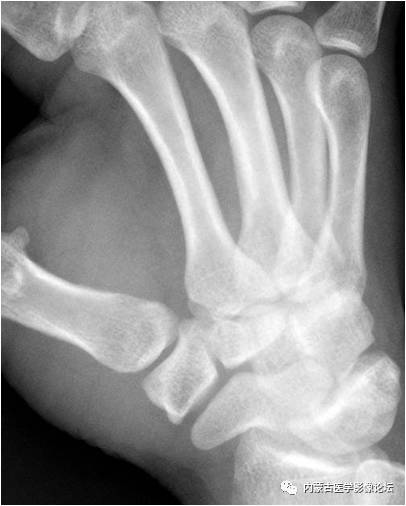

拇指掌腕关节“台阶征”:手正位片上(相当于拇指掌腕关节斜位),拇指掌腕关节的外形有一定程度的失真,关节边缘(箭)形成“台阶”样改变,与“半脱位”征象类似。手斜位片(相当于拇指掌腕关节正位)可以证实正位所见为假象。

拇指掌腕关节半脱位:手正位片示拇指掌腕关节呈“台阶”样改变,手斜位片证实为拇指掌腕关节半脱位。